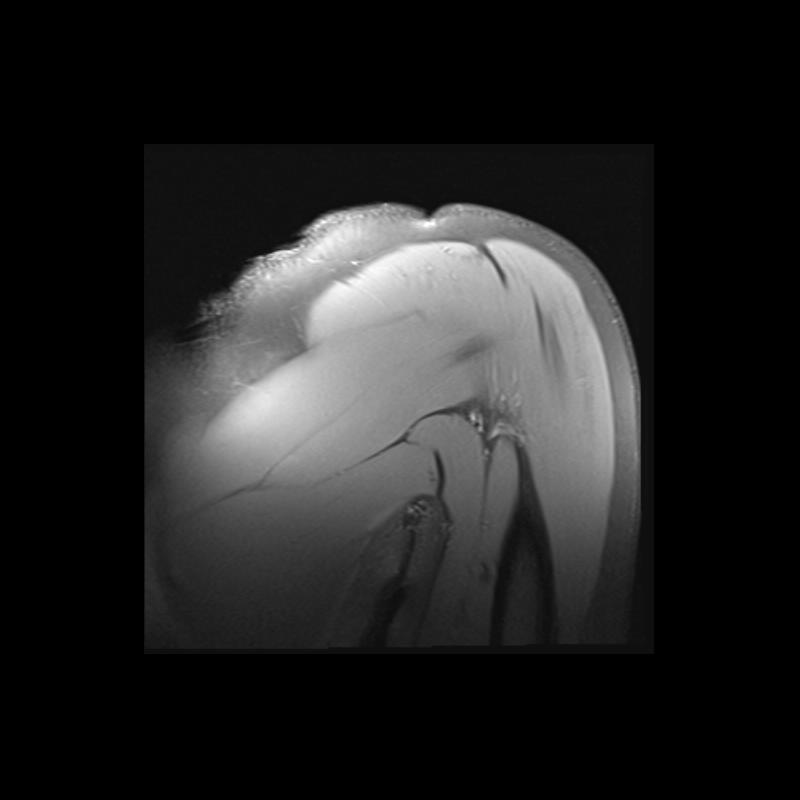

Shoulder MRI Anatomy